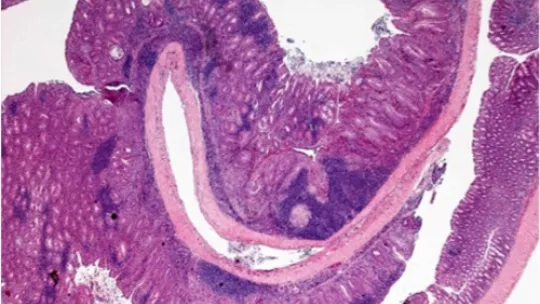

Una de les associacions millor documentades entre inflamació crònica i tumorogènesi és dóna en el càncer colorectal de pacients que pateixen inflamació de l’intestí.

El càncer colorectal és el tercer més comú al món. Els pacients amb la malaltia d’inflamació d’intestí, ja sigui per colitis ulceroses o per colitis de Crohn, tenen un risc més elevat de desenvolupar aquest tipus de càncer.

En un article recent, l’equip d’Àngel R. Nebreda descriu com p38α és fonamental pel manteniment de la bona salut de l’epiteli intestinal, controla la severitat de les colitis i actua de supressor de tumors al còlon.

L’objectiu principal d’aquest projecte és investigar com p38α regula la tumorogènesi colorectal associada a colitis. Els resultats permetran entendre el paper de p38α i els seus efectors en la biologia del càncer, així com la interacció entre les cèl·lules epitelials i del teixit, per tal d’estimar el seu valor com a diana terapèutica o marcador de diagnòstic.